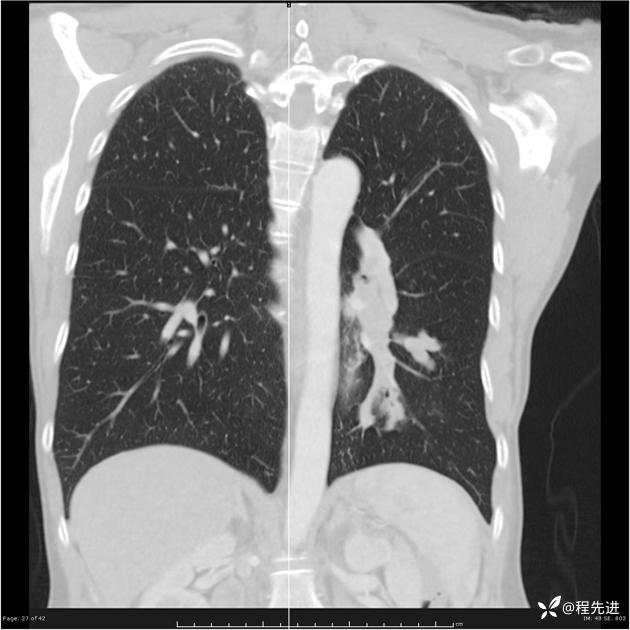

病例女,53岁,气管、左主支气管、下叶支气管内结节,乳头状瘤?期待你的精彩解读

女,53岁

乳头状瘤?